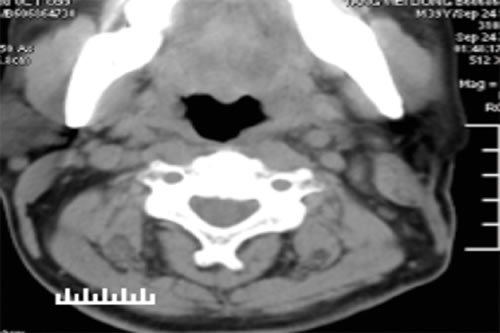

CT scans of the neck performed before and after the surgery and IORT show the beneficial structural effects of the treatment (Figures 1 and 2). Other beneficial effects of IORT were relief symptoms (tracheal compression) and impoved quality of life. One patient with poorly differentiated thyroid carcinoma relapsed after 5 months, one developed a postoperative tracheal skin fistula, and one developed wound infection. No other adverse effects were not found. Five patients experienced mild nausea and vomiting on the first day after surgery. Because patients received both surgical resection and radiotherapy, it is difficult to know whether the surgery or the radiotherapy led to the reported adverse effects.

Figure 1: Preoperative CT scan of the neck. Left thyroid mass (long arrow). Multiple enhanced lymph nodes were found in the periphery of the thyroid gland and in the left carotid sheath (short arrow).

Figure 2: CT scan of the neck 6 months after surgery. Note the absence of the left cervical mass and abnormal lymph nodes seen prior to treatment.